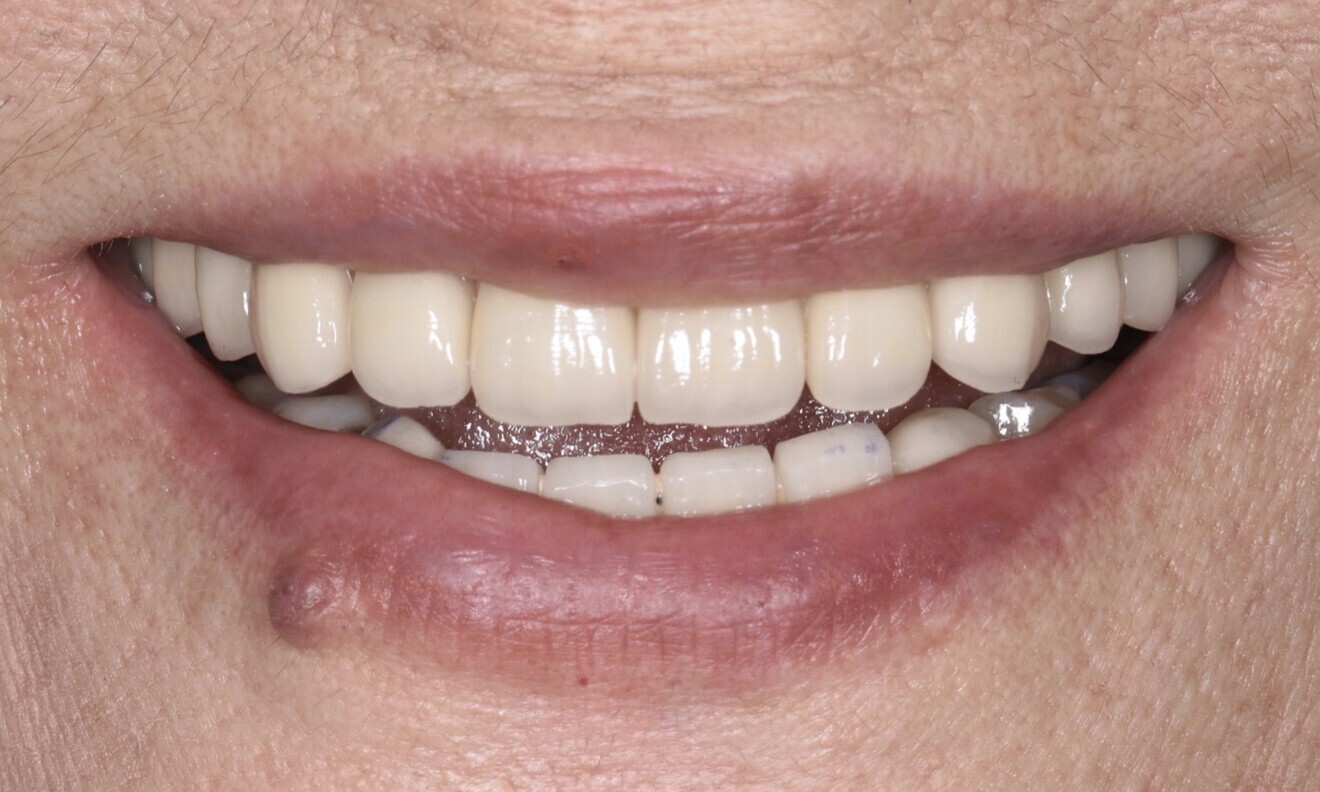

Fig. 2

The extra-oral examination showed a low smile line, and the intra-oral examination found a removable bridge from tooth #13 to tooth #23 that was poorly adapted and showed signs of deterioration. The maxillary teeth, with the exception of tooth #18, were mobile. Generalised gingival inflammation, bleeding on probing and dental caries were also present (Fig. 1). The radiographic examination exposed severe bone loss in the posterior of the maxillary left quadrant, as well as caries and apical lesions on maxillary teeth (Fig. 2).

An open-tray impression was taken, leading to the acquisition of the final cast models. These models were then utilised to create the final prosthesis. A comprehensive assessment was conducted of the prosthesis to ensure a precise and passive fit during the clinical evaluation. Furthermore, functionality, phonetics, occlusion and aesthetics were meticulously verified (Fig. 13). The screw access holes were filled using Filtek Supreme resin (3M ESPE). Oral hygiene instructions were given, and periodontal supportive therapy was scheduled for every three to four months.

After two years, clinical and radiographic control of the rehabilitation was carried out (Figs. 14 & 15). The soft and hard tissue surrounding the implant exhibited favourable conditions. Furthermore, the patient had gained a deeper understanding of her oral health and acquired knowledge on how to maintain proper oral care.

The patient expressed great satisfaction with the outcomes achieved. She could now enjoy eating without any concerns. Similarly positive outcomes were achieved across the functional, biological and aesthetic aspects.